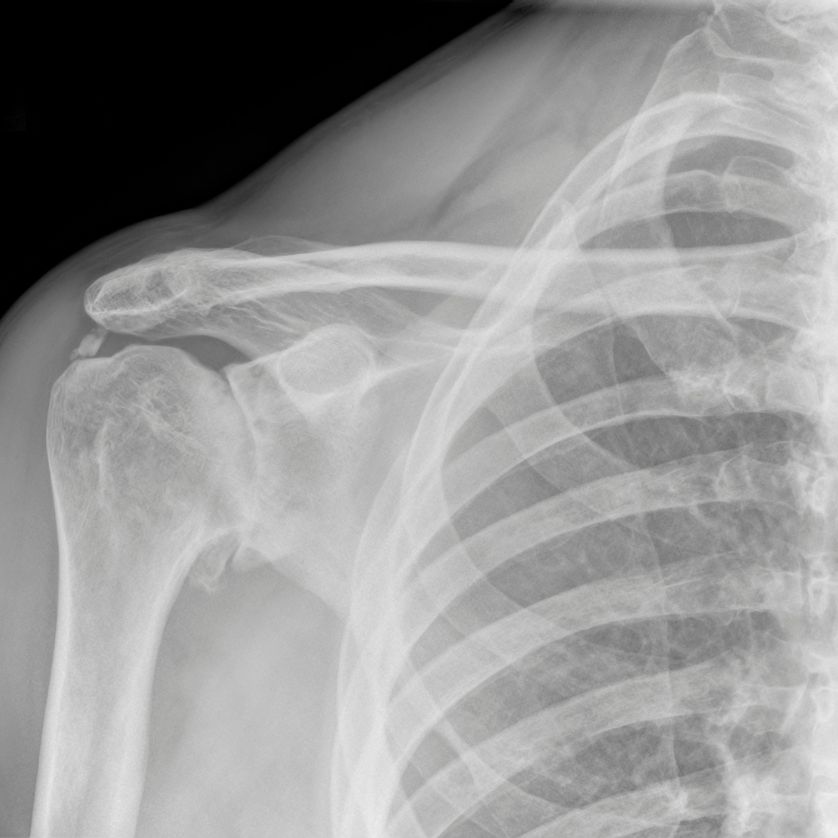

La osteoartrosis de hombro, o artrosis glenohumeral, es una enfermedad degenerativa que afecta la articulación entre la cabeza del húmero y la cavidad glenoidea de la escápula. Se caracteriza por el desgaste progresivo del cartílago articular, lo que provoca dolor, rigidez y pérdida de funcionalidad. Esta afección es menos común que la artrosis de rodilla o cadera, pero puede afectar significativamente la calidad de vida de los pacientes.

El manejo de la osteoartrosis de hombro depende de la severidad de los síntomas y el grado de desgaste articular. El tratamiento conservador es eficaz en etapas tempranas, mientras que la cirugía, especialmente la artroplastia total o inversa, ofrece soluciones definitivas para casos avanzados.